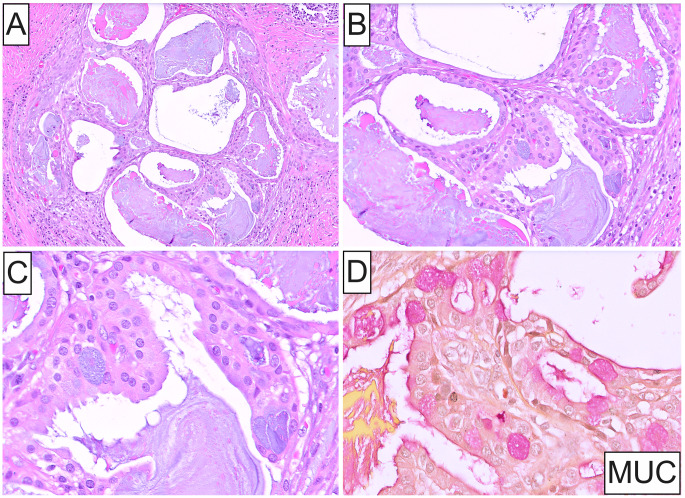

Case presentation: A 30-year-old man presented with a multilobulated left parotid mass measuring 5.2 × 4.1 × 2.4 cm by imaging, and numerous enlarged left cervical lymph nodes, suspicious for metastasis. FNA cytopathology of the mass showed loose clusters of large cells displaying increased N/C ratios and ample granular oncocytic cytoplasm. A superficial left parotidectomy with radical resection of the cheek and cervical lymphadenectomy was performed. Histopathologic examination disclosed a circumscribed, unencapsulated neoplasm exhibiting a solid growth pattern composed of infiltrative islands and nests of cohesive, polygonal, oncocytoid cells in a densely fibrous stroma. Lesional cells exhibited enlarged, oval, open-face nuclei with coarse chromatin and a single acidophilic macronucleolus, voluminous eosinophilic granular cytoplasm and distinct cell membrane borders. Mitotic activity and necrosis were absent. Microcystic architecture was noted solely in a single tumor nest at the periphery. These spaces contained mucinous secretions and were lined by cuboidal oncocytic and intermediate cells with interspersed mucocytes, highlighted by mucicarmine stain. Immunohistochemically, oncocytic cells were strongly and diffusely positive for cytokeratin AE1/AE3, p63 and p40, and uniformly negative for androgen receptor, GATA3, S100, SOX10 and Her-2. A MAML2 rearrangement was identified by FISH, thus confirming the diagnosis of oncocytic variant of mucoepidermoid carcinoma.

Conclusion: In this illustrative example, we present the clinicoradiologic, cytologic, histopathologic, and immunophenotypic characteristics of this rare variant of mucoepidermoid carcinoma, together with molecular documentation.